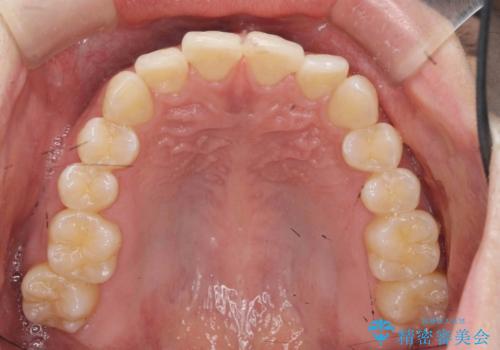

- 20代男性

- ワイヤー

- 10ヶ月

- 取り外しの必要なマウスピース矯正ではなくワイヤー矯正を希望され来院されました。

マウスピース矯正、ワイヤー矯正どちらの方法でも治療は可能ですが、ご要望の通りワイヤー矯正で歯の排列を行っていきます。